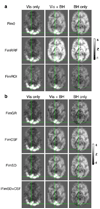

Variations in the subject's heart rate and breathing pattern have been shown to result in significant fMRI signal changes, mediated in part by non-neuronal physiological mechanisms such as global changes in levels of arterial CO(2). When these physiological changes are correlated with a task, as may happen in response to emotional stimuli or tasks that change levels of arousal, a concern arises that non-neuronal physiologically-induced signal changes may be misinterpreted as reflecting task-related neuronal activation. The purpose of this study is to provide information that can help in determining whether task activation maps are influenced by task-correlated physiological noise, particularly task-correlated breathing changes. We also compare different strategies to reduce the influence of physiological noise. Two paradigms are investigated--1) a lexical decision task where some subjects showed task-related breathing changes, and 2) a task where subjects were instructed to hold their breath during the presentation of contrast-reversing checkerboard, an extreme case of task-correlated physiological noise. Consistent with previous literature, we find that MRI signal changes correlated with variations in breathing depth and rate have a characteristic spatial and temporal profile that is different from the typical activation-induced BOLD response. The delineation of activation in the presence of task correlated breathing changes was improved either by independent component analysis, or by including specific nuisance regressors in a regression analysis. The difference in the spatial and temporal characteristics of physiological-induced and neuronal-induced fluctuations exploited by these strategies suggests that activation can be studied even in the presence of task-correlated physiological changes.